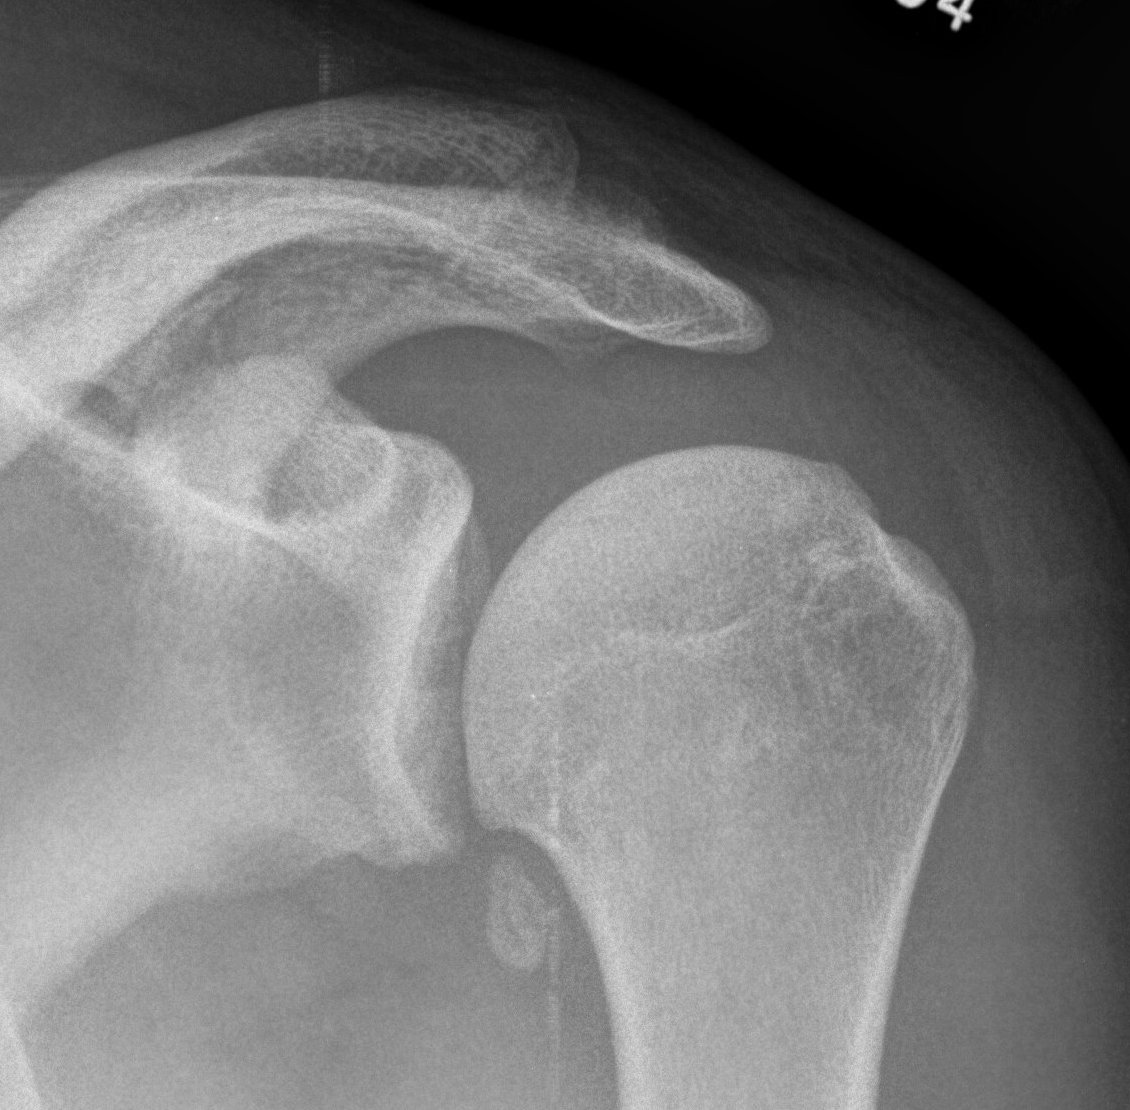

Differential diagnosis

Cuff arthopathy

- proximal migration of head

- subacromial sclerosis / acetabularization of acromion